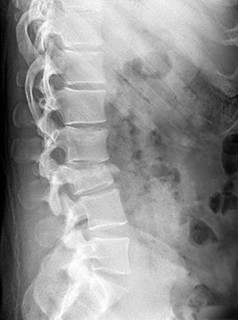

Question 11:

A 14-year-old female presents for operative evaluation of adolescent idiopathic scoliosis. Standing full-length spine radiographs show a main thoracic curve of 55 degrees and a lumbar curve of 35 degrees. The proximal thoracic curve is 20 degrees. On side-bending radiographs, the main thoracic curve corrects to 30 degrees, the lumbar curve corrects to 15 degrees, and the proximal thoracic curve corrects to 5 degrees. Based on the Lenke classification, what is the correct curve type?

Explanation:

In the Lenke classification system, a curve is considered structural if it fails to correct to < 25 degrees on side-bending radiographs or has an associated regional kyphosis > +20 degrees. Here, the lumbar curve corrects to 15 degrees (non-structural) and the proximal thoracic corrects to 5 degrees (non-structural). The main thoracic curve is the major curve (largest magnitude, 55 degrees). A major main thoracic curve with non-structural minor curves is classified as a Lenke Type 1.